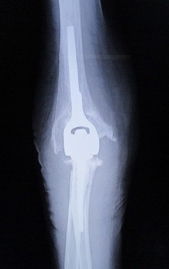

関節リウマチ

リウマチによる手・肘の変形に対する治療は一般的に難易度が高く、また習熟している施設は限られています。当院ではリウマチ手指や肘に対する人工関節手術を積極的に行い、良好な治療成績を得ています。また比較的若年の方で関節面が保たれている場合は可能な限り関節温存手術を行います。当院の担当医はリウマチ指の人工関節手術、人工肘関節手術、人工関節を用いない手指軟部組織形成術や肘関節形成術の経験も豊富です。

変形性関節症

非荷重関節である上肢の関節は腰や膝などと異なり変形する頻度は低いですが、高齢化に伴いその頻度は少しずつ増えています。またスポーツやいわゆる肉体労働をされる方においては若年であっても変形することがあります。変形性関節症に対する関節鏡手術、人工関節手術も積極的に行っています。とくに肘の関節鏡手術は手術侵襲が小さい割には術後の満足度は高く、慢性的な肘の痛みでお悩みの方は一度ご相談いただければと思います。